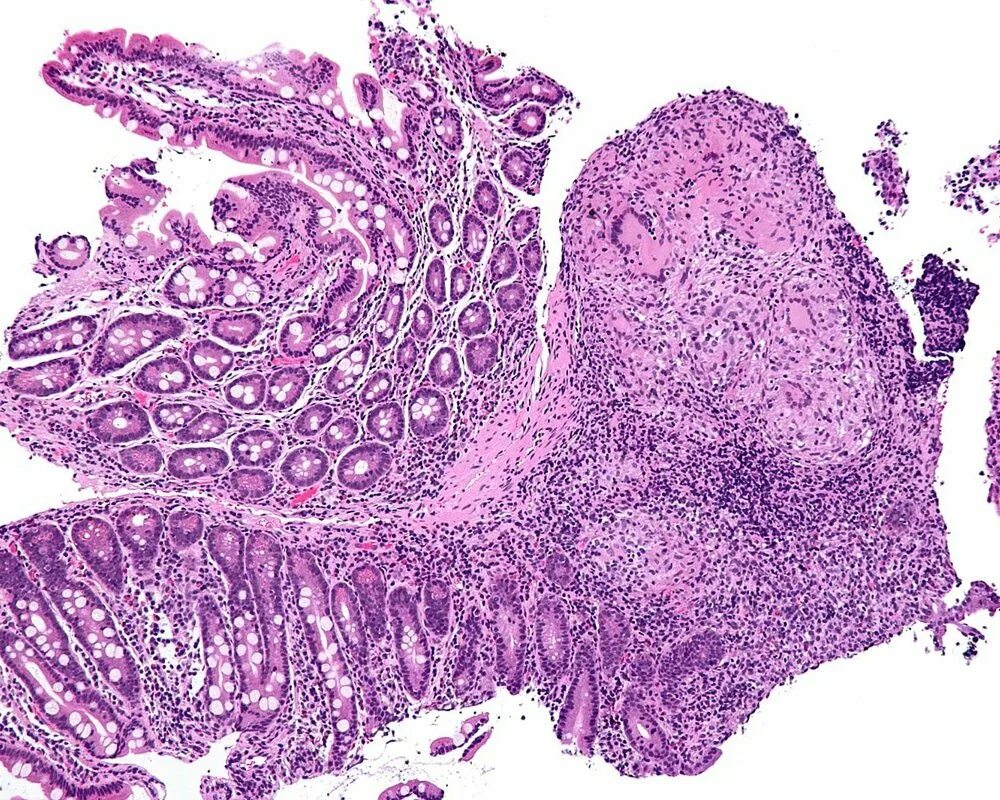

Гистологическая картина